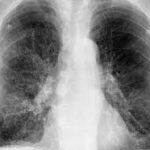

La intoxicación por bloqueadores beta-adrenérgicos es un fenómeno clínico complejo que se asocia a la administración excesiva o inadecuada de fármacos que actúan sobre los receptores beta-adrenérgicos del sistema nervioso…